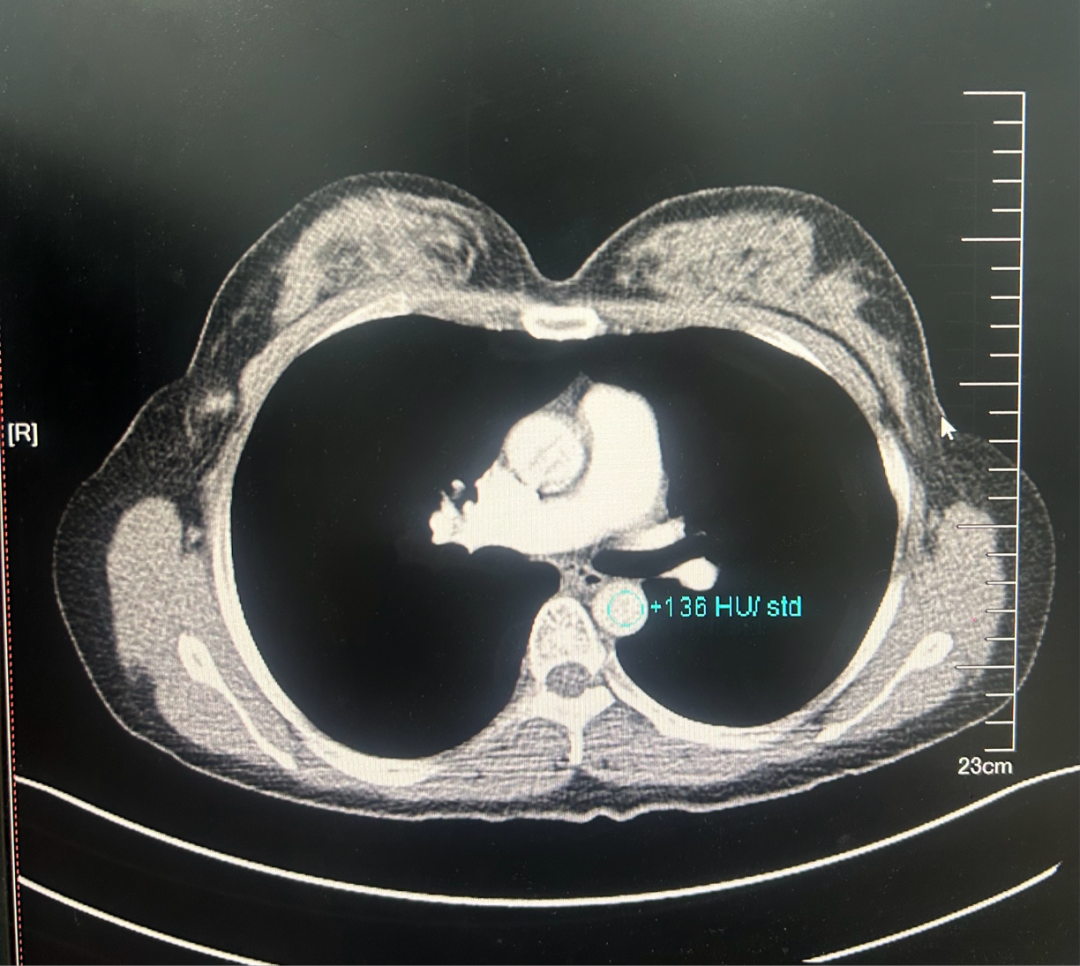

·乳腺彩超

2023-06-26彩色多普勒超声宽景成像+术前体表定位:

1、左乳4点钟方向实性肿块(乳腺Ca可能,BI-RADS 4C类),已体表定位,此次定位仅供手术医生参考。

2、双乳乳腺增生症。

3、双侧腋窝探及多个淋巴结。

图1.2023年6月24日乳腺彩超

·CT

图4.2023年6月27日CT结果

1、双肺肺气肿并散在肺大疱。

2、双肺多发微小结节,多为磨玻璃结节,密切随诊。

3、左乳外份肿块,建议乳腺相关检查。